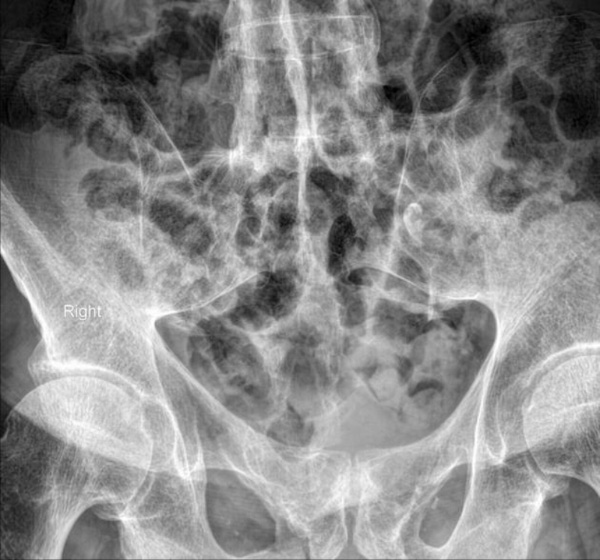

Chụp X-quang là phương pháp chẩn đoán hình ảnh viêm cột sống dính khớp được thực hiện đầu tiên giúp phát hiện các dấu hiệu viêm khớp cùng chậu, dính khớp cột sống và các thay đổi xương khác:

Hình ảnh X-quang viêm cột sống dính khớp có thể cho thấy các dấu hiệu như xói mòn xương, hình vuông hóa đốt sống, cầu xương (syndesmophytes) và dính khớp. Tuy nhiên, cần lưu ý rằng X-quang có độ nhạy hạn chế trong giai đoạn sớm của bệnh, khi các tổn thương viêm chưa gây ra thay đổi cấu trúc xương rõ ràng.

Sau đây là một số hình ảnh viêm cột sống dính khớp trên X-quang: